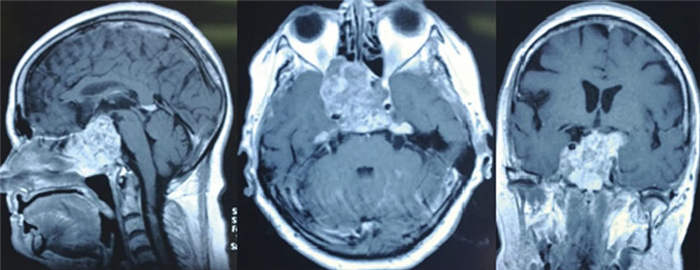

- Магнитно-резонансная томография. Обследование проводится при любом расположении хордомы, но максимально точным является при диагностике опухоли, локализованной в головном мозге. МРТ позволяет определить размер, структуру, форму и распространение хордомы. Важным преимуществом магнитно-резонансной томографии является оценка взаимоотношения опухоли с мозгом и питающими сосудами.

Диагностика

В большинстве случаев поводом для обследования становятся жалобы пациента на головные боли или неврологические нарушения. Ведущий метод диагностики — МРТ с контрастированием, достаточно точно характеризующая внутреннее строение новообразования и взаимоотношения с окружающими структурами.